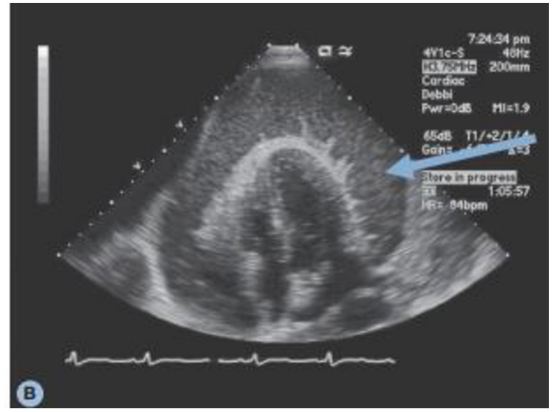

Observe a imagem, abaixo, e indique sua interpretação entre as alternativas:

Fonte: https://statics-submarino.b2w.io/sherlock/books/firstChapter/113916111.pdf